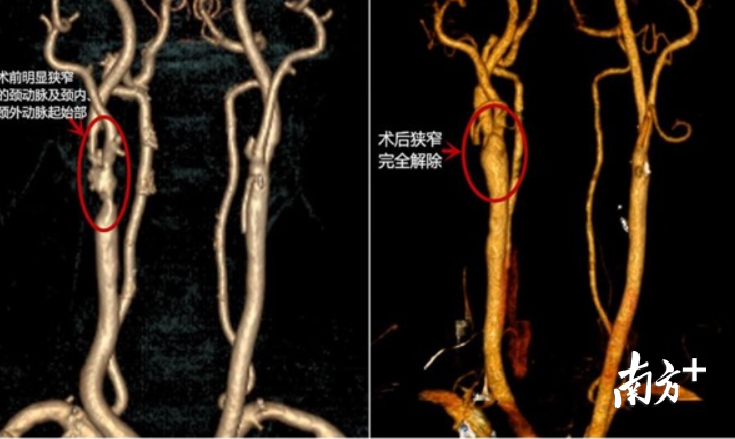

日前,中大五院心血管外科主任李刚带领的团队进行术中探查,发现韩某的病变非常严重,右侧颈动脉无明显搏动,管腔内基本被斑块堵死,经过约2个小时的努力,他们将所有斑块全部清除,该患者颈动脉又恢复了跳动。

“手术好像脱袜子一样将颈动脉的外膜翻开,显露并切除病变的内膜,清除堵塞血管的‘垃圾’。打开堵塞的血管,使颈动脉的内壁光滑、内径恢复正常大小,脑血管得以疏通,有效改善了脑供血不足的情况,同时切断了栓子产生的来源,然后再将外膜缝合到原来的位置上。”李刚表示,患者术后未出现并发症,恢复顺利,术前的不适症状得到明显改善,已从ICU转入普通病房,不久便可痊愈出院。